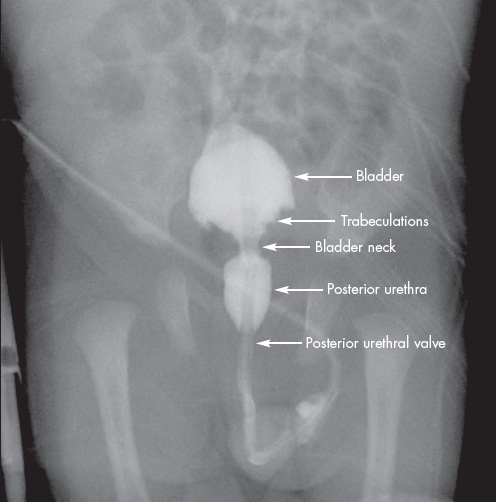

Posterior urethra valves is the most common cause of bladder outlet obstruction in male newborns resulting from an obstructing membrane in the posterior urethra from abnormal in utero development.

Posterior urethra valves is diagnosed with voiding cystourethrogram (VCUG), which is characterized by an abrupt tapering of urethral caliber. It is associated with vesicoureteral reflux in 50% of children. Diagnosis can also be made by cystoscopy by direct visualization.

The treatment for posterior urethra valves is surgical endoscopic valve ablation. In select cases, fetal surgery is necessary for those with severe oligohydramnios, in an attempt to limit the associated lung underdevelopment that is seen at birth.